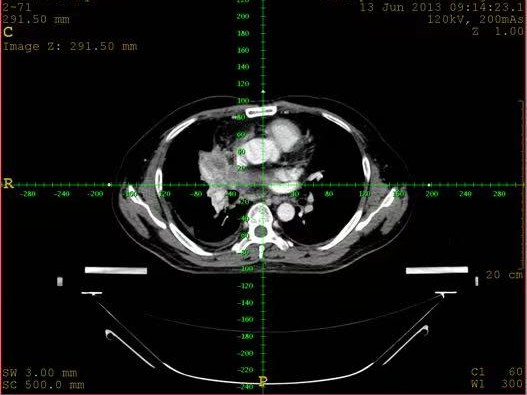

三是定位的精准度更高。具有强大的图像处理功能,能准确反映肿瘤范围和周围危险器官的轮廓,更准确地定位肿瘤靶区,完成对肿瘤的精准治疗,减少对其他组织的损伤率。

四是应用范围较广。大孔径CT由于孔径大,方便操作,图像显示清晰,不仅用于肿瘤放疗诊断治疗,同时也用于CT引导下肿瘤定位、穿刺活检及介入治疗等方面。